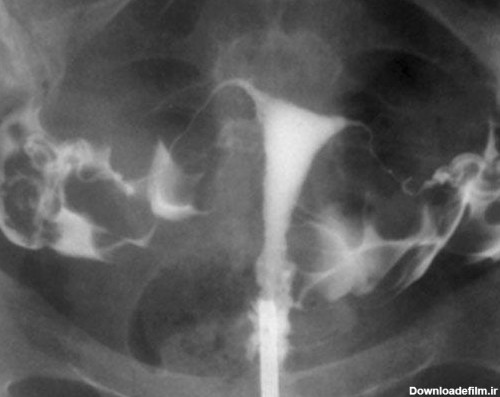

برای بررسی علت تأخیر باروری، باید سلامت اندامهای تولید مثل مورد ارزیابی قرار گیرند؛ یکی از روشهای تشخیصی که برای بررسی رحم و لولههای رحمی درخواست می شود، هیستروگرافی است. با این تست، پزشک از وضعیت داخلی رحم و لوله های رحمی مطلع میگردد و با توجه به نتایج حاصل از تست، در مورد نحوه درمان تصمیم خواهد گرفت. انجام این تست در ارزیابی ناباروری بسیار مهم است.

عکس رنگی رحم یا هیستروسالپنگوگرافی روشی است که به منظور بررسی داخل رحم و لوله های رحمی انجام می گیرد و انجام آن در ارزیابی ناباروری بسیار مهم است.